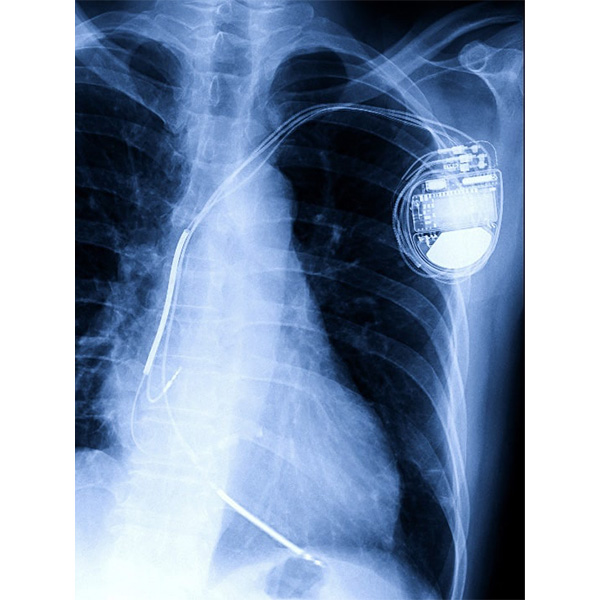

ペースメーカー植込み

心臓の動きを感知して、脈が遅い場合には電気刺激が流れて心臓を刺激し、脈を作り出す装置です。

一般的には局所麻酔で手術を行い、手術時間は90分程度です。鎖骨下静脈から電極のついたリードを右心房と右心室内に挿入し、ペースメーカー本体につなぎ、本体を皮下に植え込みます。